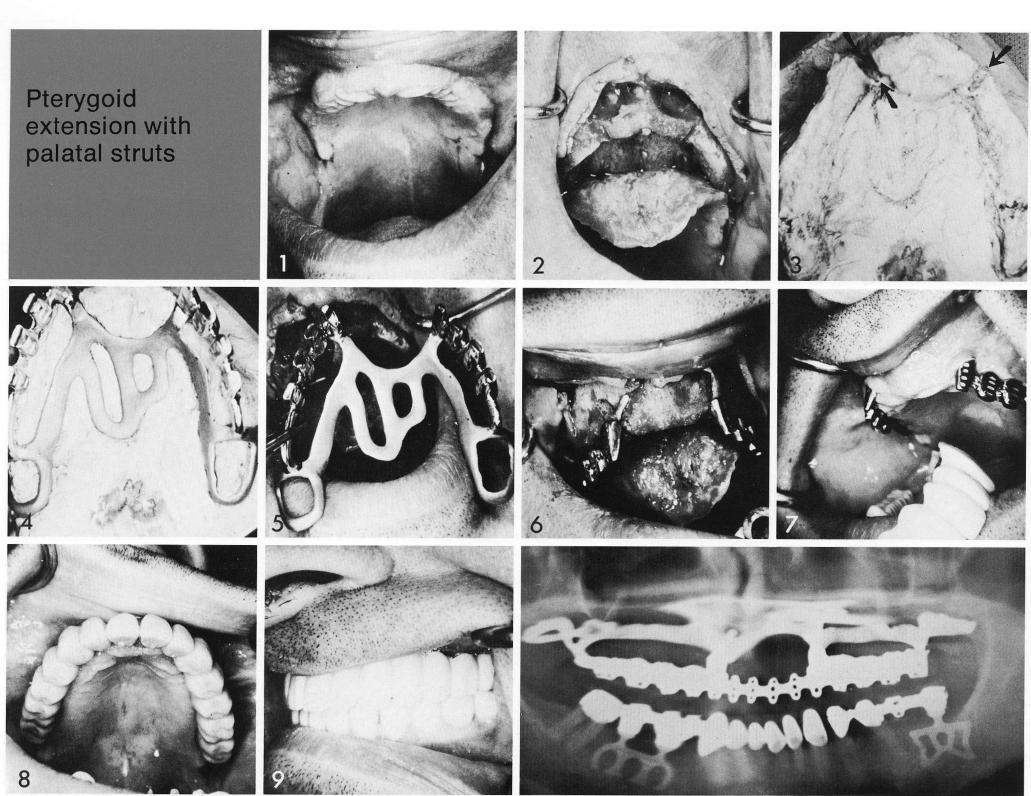

Pterygoid extension with

palatal struts

Soft tissues padded (1) a very severely undercut anterior ridge (2). Deep grooves were made across the bony ridge, and an impression taken which clearly showed their depths. The finished implant (4) was inserted (5,6), and later the full-arch palateless restoration (7,8). As with any form of dentition, proper occlusion is important (9).

1 Very severely maxillary anterior ridge undercut for implantation